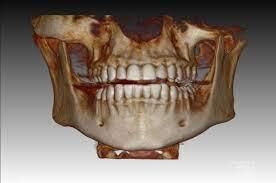

3 Boyutlu görüntüleme (Dental tomografi)

Dental tomografi, diş hekimliği uygulamalarında kullanılan yüksek çözünürlüklü üç boyutlu görüntüler elde etmek için kullanılan ileri radyolojik bir teknolojidir. Bu teknoloji, diş ve çene yapısının detaylı bir şekilde incelenmesini sağlayarak implant planlaması, çene cerrahisi ve diş kökü tedavileri gibi karmaşık işlemlerin daha hassas bir şekilde planlanmasına yardımcı olur. Özellikle implant cerrahilerinde altın standartta bir ileri görüntüleme yöntemidir. Dental tomografi, diş hekimlerine daha doğru teşhis koyma ve tedavi planlaması yapma imkânı sunarak hastalara daha etkili ve kişiselleştirilmiş bir ağız sağlığı hizmeti sunar.